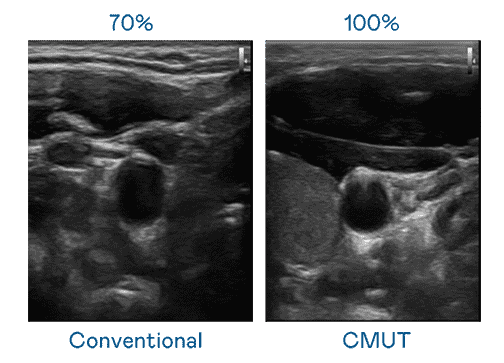

CMUT 技术是一种用电容式微机电元件来产生超音波讯号的技术。。。与传统 PZT 压电式技术相比,,,CMUT 频宽增加 30%,,,,更宽频的超音波讯号让影像解析度大幅提升,,,是实现高影像品质医疗超音波扫描、、、、促进精准医疗发展的关键技术。。。

大频宽带来超清晰影像

超音波影像的解析度高低,,,首先取决于探头能发出的讯号频宽。。尊龙z6 CMUT 可提供高清晰的超音波讯号,,,,提供高频宽、、、高灵敏度、、影像纹理细节更高的超音波影像,,协助医护人员缩短影像判读时间及利用精准的医疗影像进行诊断。。。。